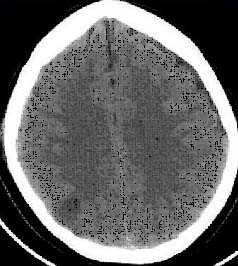

По причине мягкой семиотики сотрясения головного мозга и возможности возникновения подобной картины в результате одной из многих дотравматических патологий, особое значение в диагностике придается динамике клинических симптомов. Обоснованием диагноза «сотрясение мозга» является исчезновение таких симптомов через 3-6 суток после получения черепно-мозговой травмы. При сотрясении мозга отсутствуют переломы костей черепа. Состав ликвора и его давление сохраняются в норме. На КТ головного мозга не определяются внутричерепные пространства.

Всех пострадавших с черепно-мозговой травмой в обязательном порядке транспортируют в стационар, где после подтверждения диагноза устанавливают им постельным режим на срок, который зависит от клинических особенностей течения заболевания. Отсутствие признаков очаговых поражений головного мозга на КТ и МРТ головного мозга, а также состояние пациента, позволяющее воздержаться от активного медикаментозного лечения, позволяют решить вопрос в пользу выписки пациента на амбулаторное лечение.